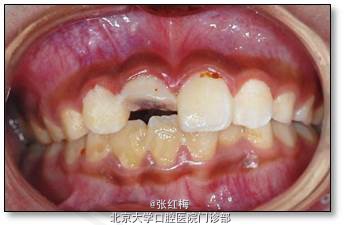

检查:11粘接断冠完好,叩(-),不松,龈未见异常,冷测有感觉,无疼痛;X线:11根 尖继续

形成中,根周膜清晰

21叩(-),不松,龈未见异常,冷测同正常对照牙。